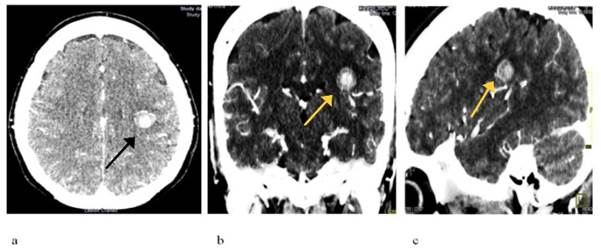

Se le realiza tomografía axial computarizada (TAC) de cráneo simple y E/V, donde se observa imagen hiperdensa, redondeada con aspecto de ovillo con densidad de 54 UH, localizada a nivel del lóbulo parietal izquierdo (Figura 1 a, b, c) y angio-TAC de cráneo donde se observa imagen hiperdensa (54 UH), redondeada con aspecto de ovillo, localizada a nivel del lóbulo parietal izquierdo en territorio de la arteria cerebral media y con drenaje a nivel del seno sagital inferior (Figura 2).

Figura 1: TAC de Cráneo Simple A (corte axial E/V), B (corte coronal E/V) , C (corte Sagital E/V). Fuente: Servicio de Imagenología del Hamad General Hospital